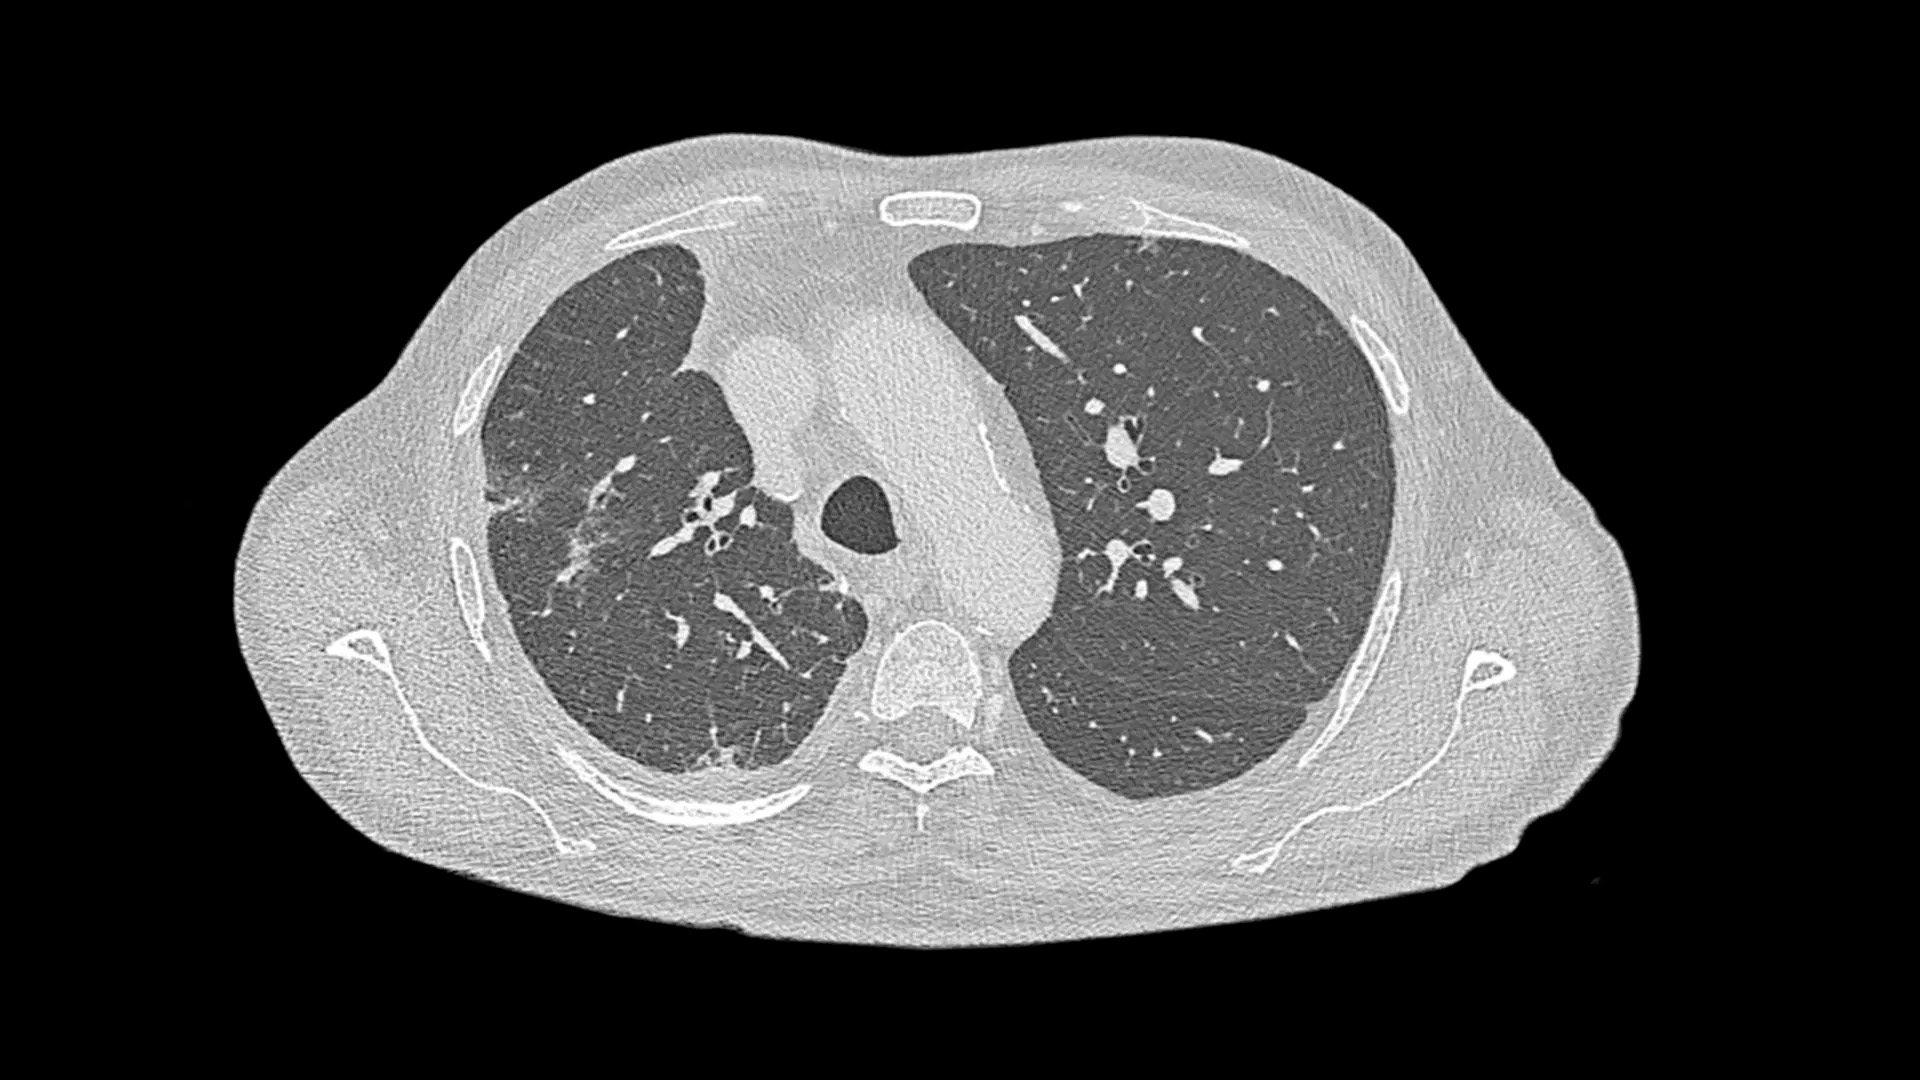

В основе NAEOTOM Alpha ® лежит радикально новый детектор. Детектор QuantaMax напрямую преобразует рентгеновские лучи в электрический сигнал, который затем используется для создания изображения. Измеряется энергия каждого рентгеновского луча, поэтому спектральная информация доступна для каждого сканирования, а изображения получаются контрастными и с высоким пространственным разрешением при той же дозе. Сочетание высокого пространственного разрешения детектора подсчета фотонов QuantaMax с временным разрешением двойного источника позволяет визуализировать мелкие детали для повышения достоверности диагностики.

Прецизионные детекторы QuantaMax

QuantaMax, первый детектор фотонов, преодолевает ограничения традиционных детекторов КТ, предоставляя данные с высоким пространственным разрешением, без электронного шума и с улучшенным соотношением контраст/шум.